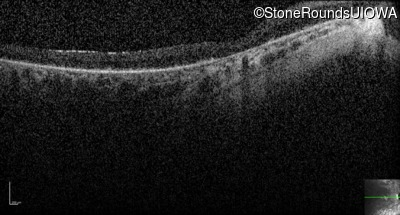

Optical Coherence Tomography - Right - 5/180

Exemplar / OCT Stack